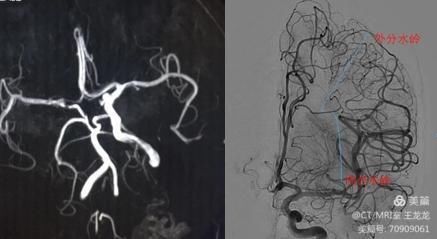

2022-03-16特色展示之九-血流导向装置在颅内复杂动脉瘤中的应用

血流导向装置(Flow Diverter FD)主要目的是最佳的改变载瘤血管和动脉瘤之间的血流,同时为血管提供一个血管内支架,以修复导致动脉瘤形成的缺陷血管。与FD功能相关的是... -